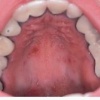

– Sümptomid vastavad trombotsüütide talitlushäiretest põhjustatud nähtudele (verevalumid, limaskestaverejooksud, kauakestvad ninaverejooksud, menstruatsiooni-liigverejooks jt.).

Von Willebrand